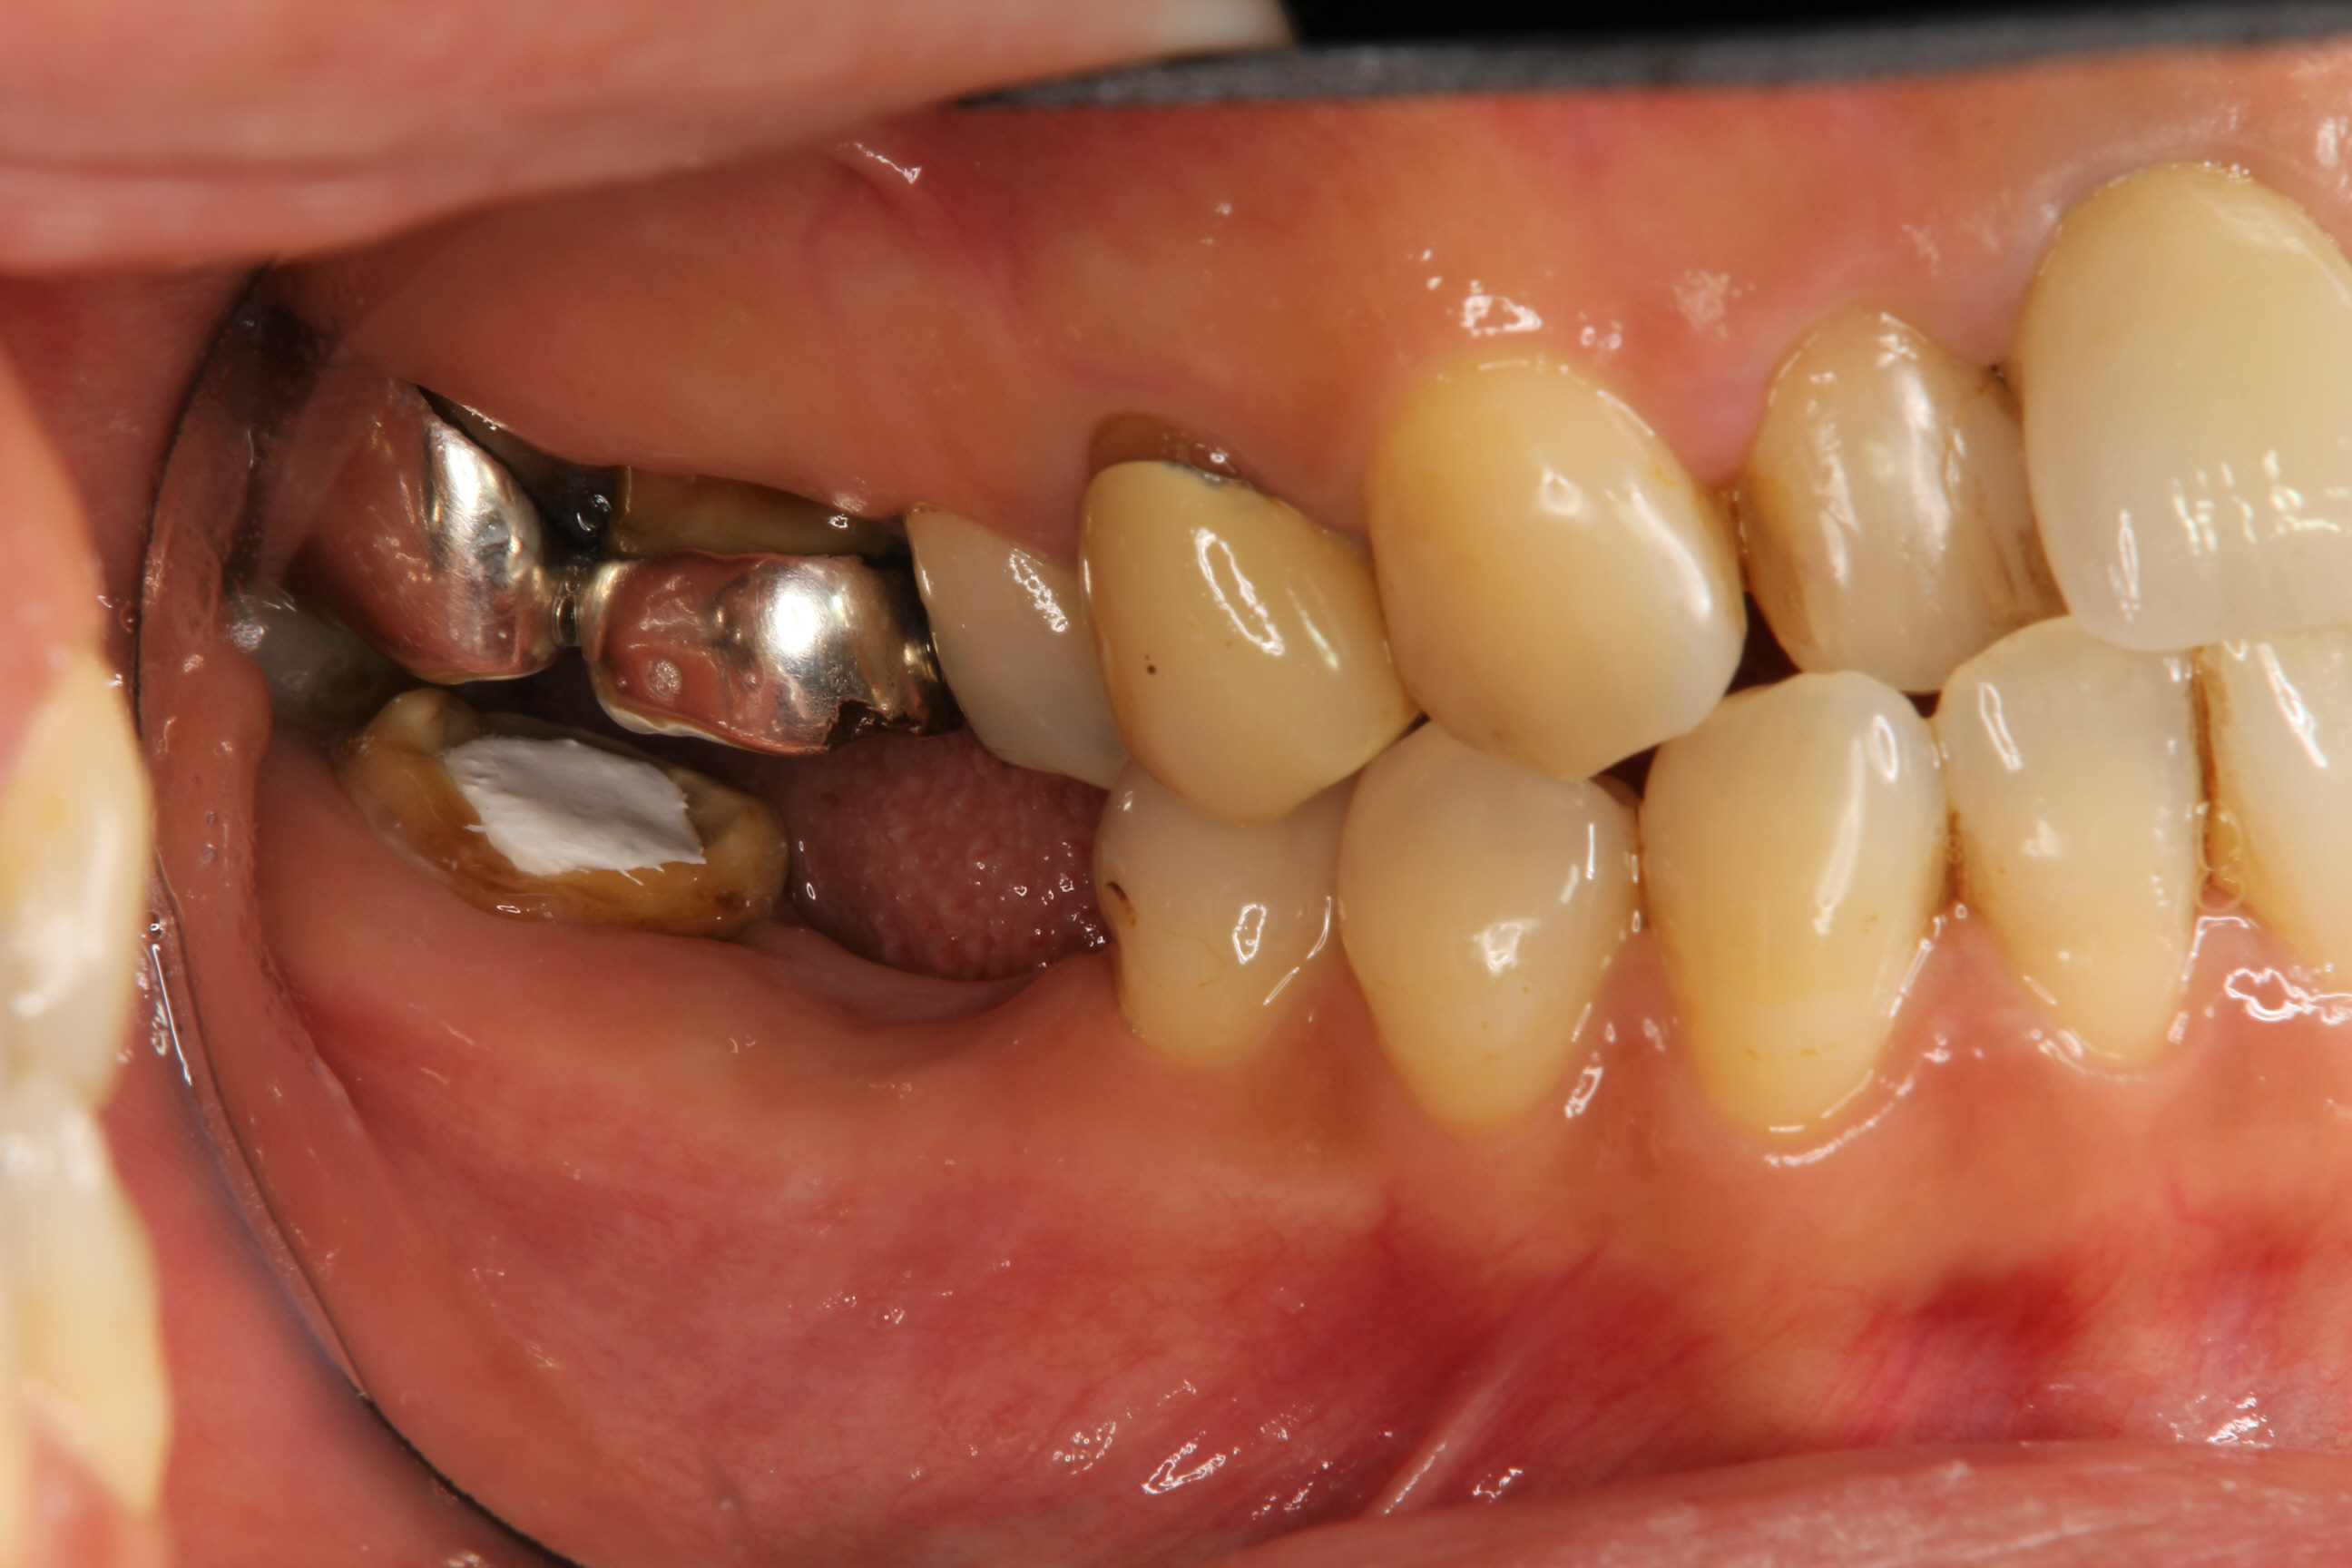

左の写真の患者さんは、奥歯のクラウンが脱離して来院された方です。

こちらの患者さんの場合は、支台になっていた歯が虫歯と破折によりボロボロになっており、抜歯せざるをえない状態でした。

頬側の歯肉を見ると、患歯だけでなく前方の歯にも腫れを認めます。